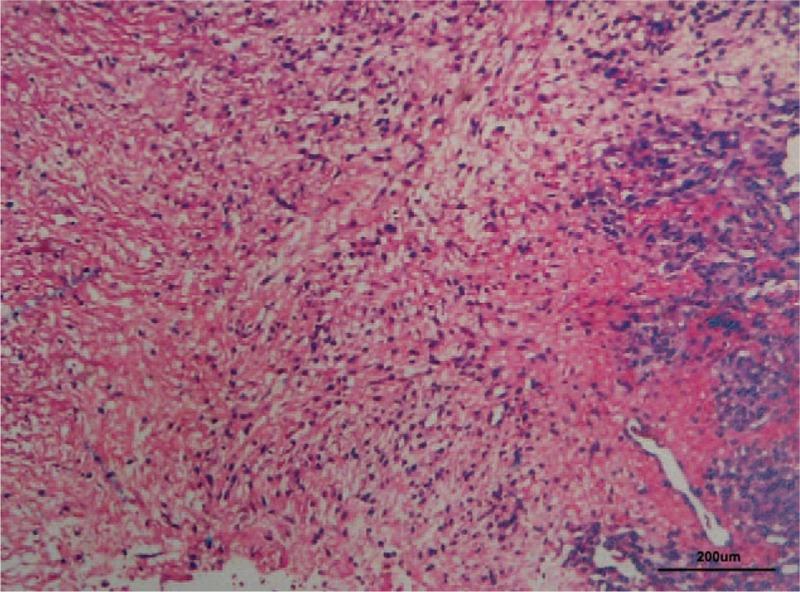

一例罕见的伴有颅骨肿块、红细胞减少和血小板减少的血管肉瘤:病例报告及文献复习

A rare case of angiosarcoma with skull masses and erythropenia and thrombocytopenia: A case report and review of literature.

Primary splenic angiosarcoma (PSA) is a rare, fatal neoplasm originating from sinusoidal vascular endothelial cells, and usually metastasizes and almost always has a poor prognosis. Surgical excision is the main treatment of this highly malignant disease.

PATIENT CONCERNS

We reported a special case of a 68-year-old female who had a 6-month history of scalp masses.

DIAGNOSIS

The patient was found to have 2 skull masses on computed tomography (CT). Laboratory findings revealed erythropenia and thrombocytopenia. Enhanced abdomen magnetic resonance imaging (MRI) showed multiple masses in liver and spleen. The pathological result of the skull masses was revealed to be metastatic angiosarcoma.

INTERVENTIONS

The patient underwent surgical excision of skull masses, and no subsequent radiotherapy or chemotherapy was done.

OUTCOMES

The patient died due to dyscrasia at August 12, 2015, with a survival of nearly 1 month.

LESSONS

We highlight the importance for clinicians to be aware of this rare neoplasm, and to consider it in the differential diagnosis when encountering a skull mass. Early confirmation and treatment may improve the prognosis.